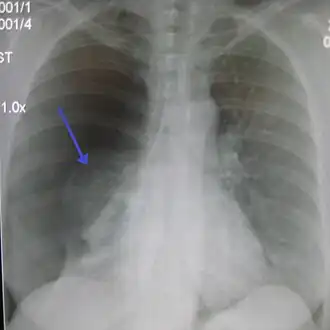

![]() Правосторонний спонтанный пневмоторакс (слева на изображении). Стрелкой указан край спавшегося лёгкого. | |

- Рентгенографическим признаком пневмоторакса является визуализация тонкой линии висцеральной плевры (менее 1 мм), отделённой от грудной клетки.